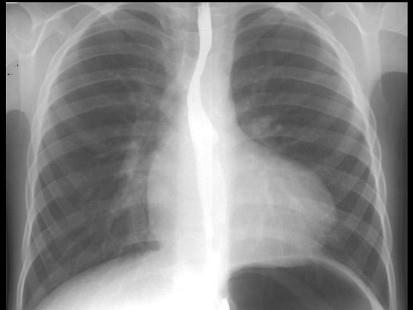

如图,X线检查表现为肺动脉段凹陷,可能为下列哪一种先天性心脏病的 ( )A、室间隔缺损B、动脉导管未闭C、肺动脉狭窄D、法洛四联症E、...